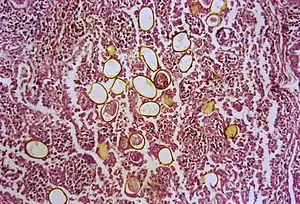

The first human case was seen in 1879 in Taiwan. An autopsy was done and adult trematodes were found in the lungs. The adult flukes have a reddish-brown in color with an ovoid shape. They have two muscular suckers, the first an oral sucker located anteriorly and the second a ventral sucker located mid-body. The adult flukes can live up to 20 years. The eggs are golden brown in color and are asymmetrically ovoid. They have a very thick shell. As seen above, these trematodes have a very complex life cycle with seven distinct phases involving intermediate hosts and humans.[10] These seven phases are outlined as follows: eggs reach fresh water where they develop into miracidia. These penetrate many species of aquatic snails (first intermediate host) where they go through three distinct stages: first sporocysts, then rediae, and finally cercariae, also referred to as the larvae. These larvae released into water and penetrate crabs, crayfish and other crustaceans (second intermediate host). The cercariae situate themselves into the gills, liver and muscles where they further develop into metacercariae. When the parasite-filled crustacean is eaten, the metacercariae hatch in the intestine. These young worms penetrate intestinal wall, peritoneum, the diaphragm and the pleura where they finally reach the lungs. Here they live in pairs, lay eggs that are coughed up in sputum to restart the cycle.[11]